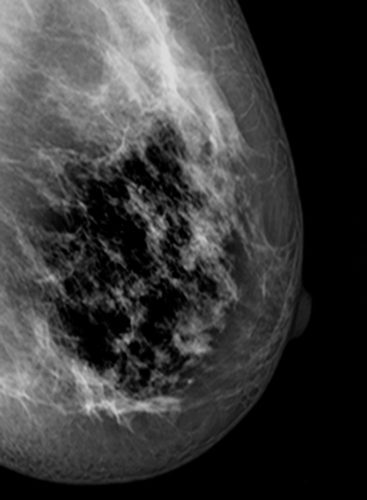

La fotógrafa madrileña María Torija ha ganado el premio expositivo (Premio PhotoWall) gracias al portfolio presentado en el visionado del domingo, donde mostró su trabajo ‘Espiral’, un proyecto fotográfico nacido de una experiencia personal en torno al cáncer de mama.

El jurado ha escogido como mejor proyecto para exposición en pared este trabajo que se desarrolla a partir de las vivencias de esta enfermedad con un enfoque poético y muy personal, trazando un recorrido de los acontecimientos desde el diagnóstico hasta su remisión a modo de diario.

El propio cuerpo es material para las fotografías, la piel se convierte en un paisaje

reflejo de los fantasmas más íntimos del inconsciente y las secuelas terapéuticas de la enfermedad, es un mapa de batallas frente a las agresiones médicas.

Las vivencias terapéuticas se desacralizan, se mimetizan con el paisaje vegetal. Las

raíces de las plantas horadan el suelo a modo de taladro en espiral, penetrando en la

tierra; igualmente las células cancerosas con el mismo movimiento en espiral atacan los tejidos sanos y se anclan a ellos mientras se expanden en la metástasis haciendo crecer los tumores.